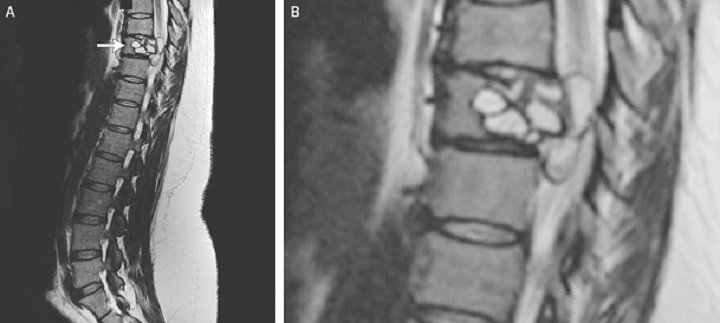

Woman complains of ‘electric shocks’ in legs, doctors find tapeworm larvae wriggling in spineA French woman whose symptoms started off as "electric shocks" on her legs found out she actually had tapeworm larvae in her spine.HealthJul 13, 2018